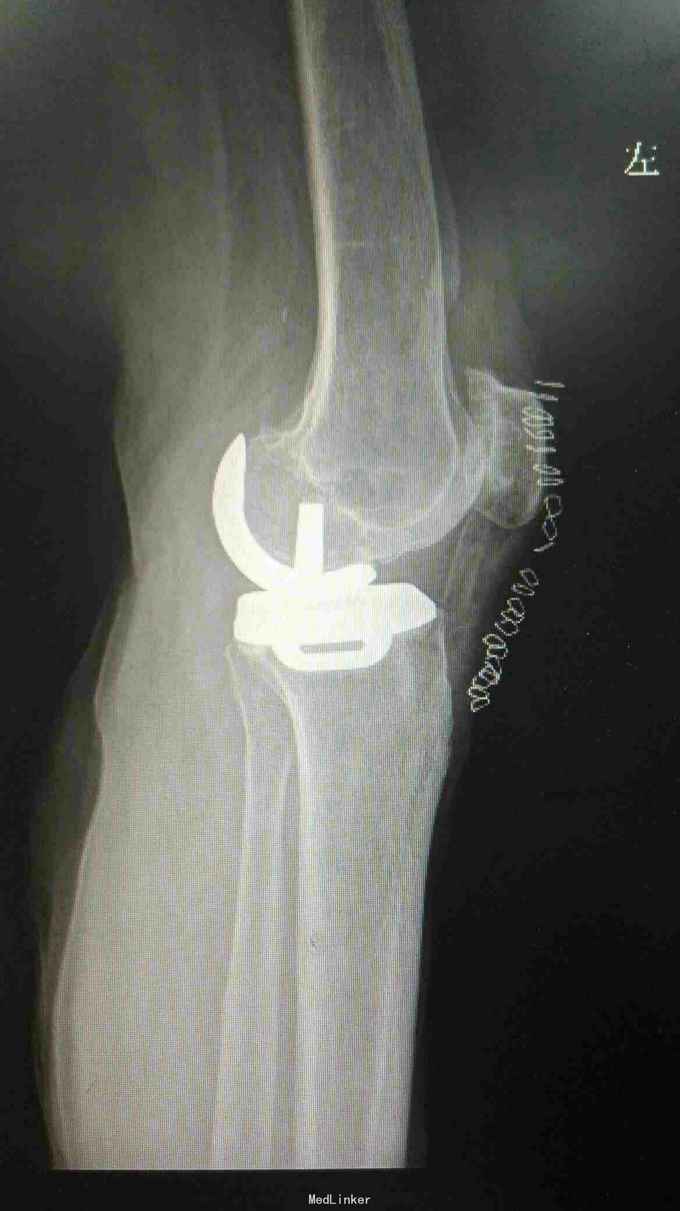

诊断:左膝关节骨性关节炎 治疗:左膝关节单髁置换术

术后第一天下地,1周出院,出院时屈伸活动度0---110度 讨论:虽然患者年龄大,但病变局限于单间室,行单髁置换仍未较合理选择,手术创伤小,恢复快。术前备用了全膝置换器械,如果前交叉韧带断裂需行全膝关节表面置换术。